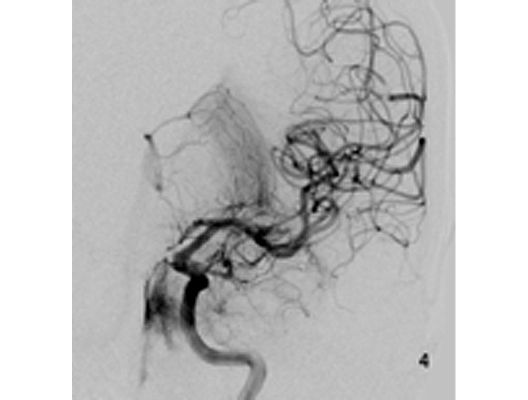

Mit den modernen Verfahren zur Wiedereröffnung von verschlossenen Blutgefäßen können wir Patienten mit Schlaganfall in vielen Fällen helfen. Das folgende Beispiel zeigt die angiographischen Bilder eines Patienten, der mit vollständiger Lähmung der rechten Körperhälfte und einer schweren Sprachstörung eingeliefert wurde. Ursächlich zeigte sich ein Verschluss der linken Halsschlagader, vermutlich auf dem Boden einer arteriosklerotischen Einengung (Bild 1). Das Gefäß wurde daraufhin mit einem Stent wiedereröffnet (Bild 2). Zusätzlich zeigte sich ein Verschluss der Endstrecke des Gefäßes durch Blutgerinnsel (Bild 3). Diese konnten vollständig entfernt werden (Bild 4). Der Patient erholte sich nach der Behandlung innerhalb weniger Tage vollständig.